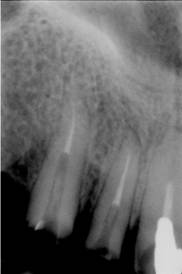

La nivelul lui 21 se observa obturatia de canal corect executata din punct de vedere radiologic. Clinic se constata obturarea canalului radicular cu ciment oxifosfat de zinc si fara con de gutaperca. Pe a doua radiografie se observa dezobturarea corecta a canalului radicular pt. realizarea unui DCR

Radiografii retroalveolare la inceputul si la sfīrsitul tratamentului endodontic